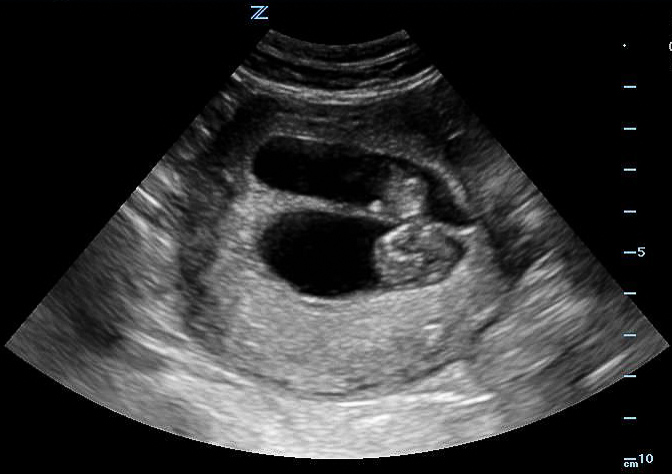

- Number of Fetuses

- Multiple pregnancies increases risk of preterm delivery, preeclampsia, abnormal labor, and intrauterine growth restriction26

- Often diagnosed by finding two fetal heads or two fetal poles in uterine cavity.

- Confirm by identifying 2 separate fetal bodies.

- Dividing membrane often seen, but not required in monochorionic-monoamniotic twins.

Figure 31. Note two separate third trimester fetal crania.